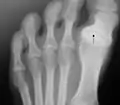

Radiography of the left foot of a young male showing progressive hallux varus Radiography of the left foot of a young male showing progressive hallux varus